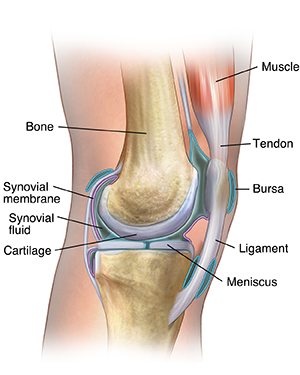

Anatomy of a Joint

Joints are the areas where 2 or more bones meet. Most joints are mobile, allowing the bones to move. Joints consist of the following:

Cartilage. This is a type of tissue that covers the surface of a bone at a joint. Cartilage helps reduce the friction of movement within a joint.

Synovial membrane. A tissue called the synovial membrane lines the joint and seals it into a joint capsule. The synovial membrane secretes a clear, sticky fluid (synovial fluid) around the joint to lubricate it.

Ligaments. Strong ligaments (tough, elastic bands of connective tissue) surround the joint to give support and limit the joint's movement. Ligaments connect bones together.

Tendons. Tendons (another type of tough connective tissue) on each side of a joint attach to muscles that control movement of the joint. Tendons connect muscles to bones.

Bursas. Fluid-filled sacs, called bursas, between bones, ligaments, or other nearby structures. They help cushion the friction in a joint.

Synovial fluid. A clear, thick fluid secreted by the synovial membrane.

Meniscus. This is a curved part of cartilage in the knees and other joints.